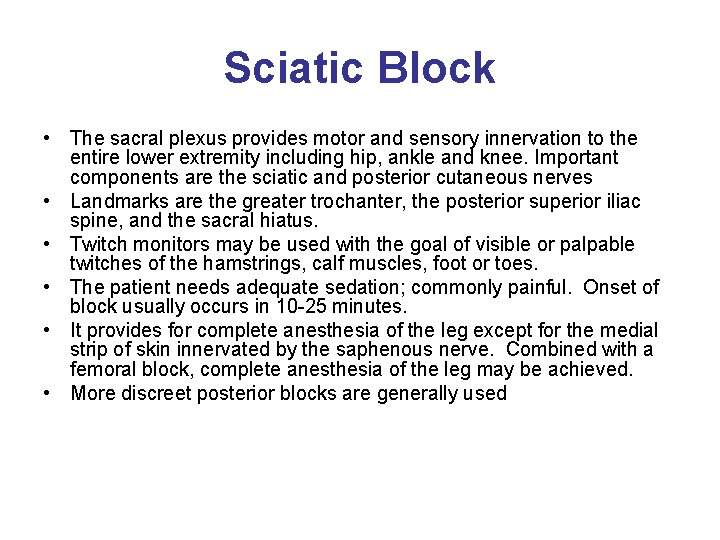

Sciatic Block • The sacral plexus provides motor and sensory innervation to the entire lower extremity including hip, ankle and knee. Important components are the sciatic and posterior cutaneous nerves • Landmarks are the greater trochanter, the posterior superior iliac spine, and the sacral hiatus. • Twitch monitors may be used with the goal of visible or palpable twitches of the hamstrings, calf muscles, foot or toes. • The patient needs adequate sedation; commonly painful. Onset of block usually occurs in 10 -25 minutes. • It provides for complete anesthesia of the leg except for the medial strip of skin innervated by the saphenous nerve. Combined with a femoral block, complete anesthesia of the leg may be achieved. • More discreet posterior blocks are generally used